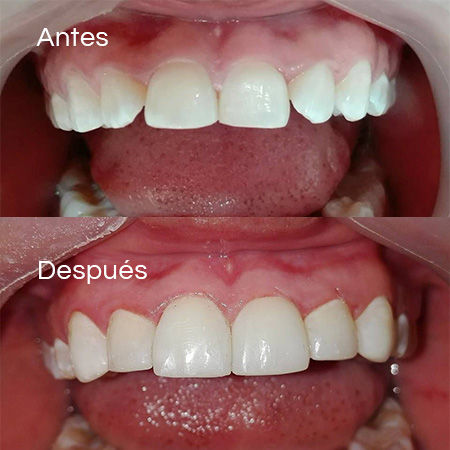

Before and After Gallery